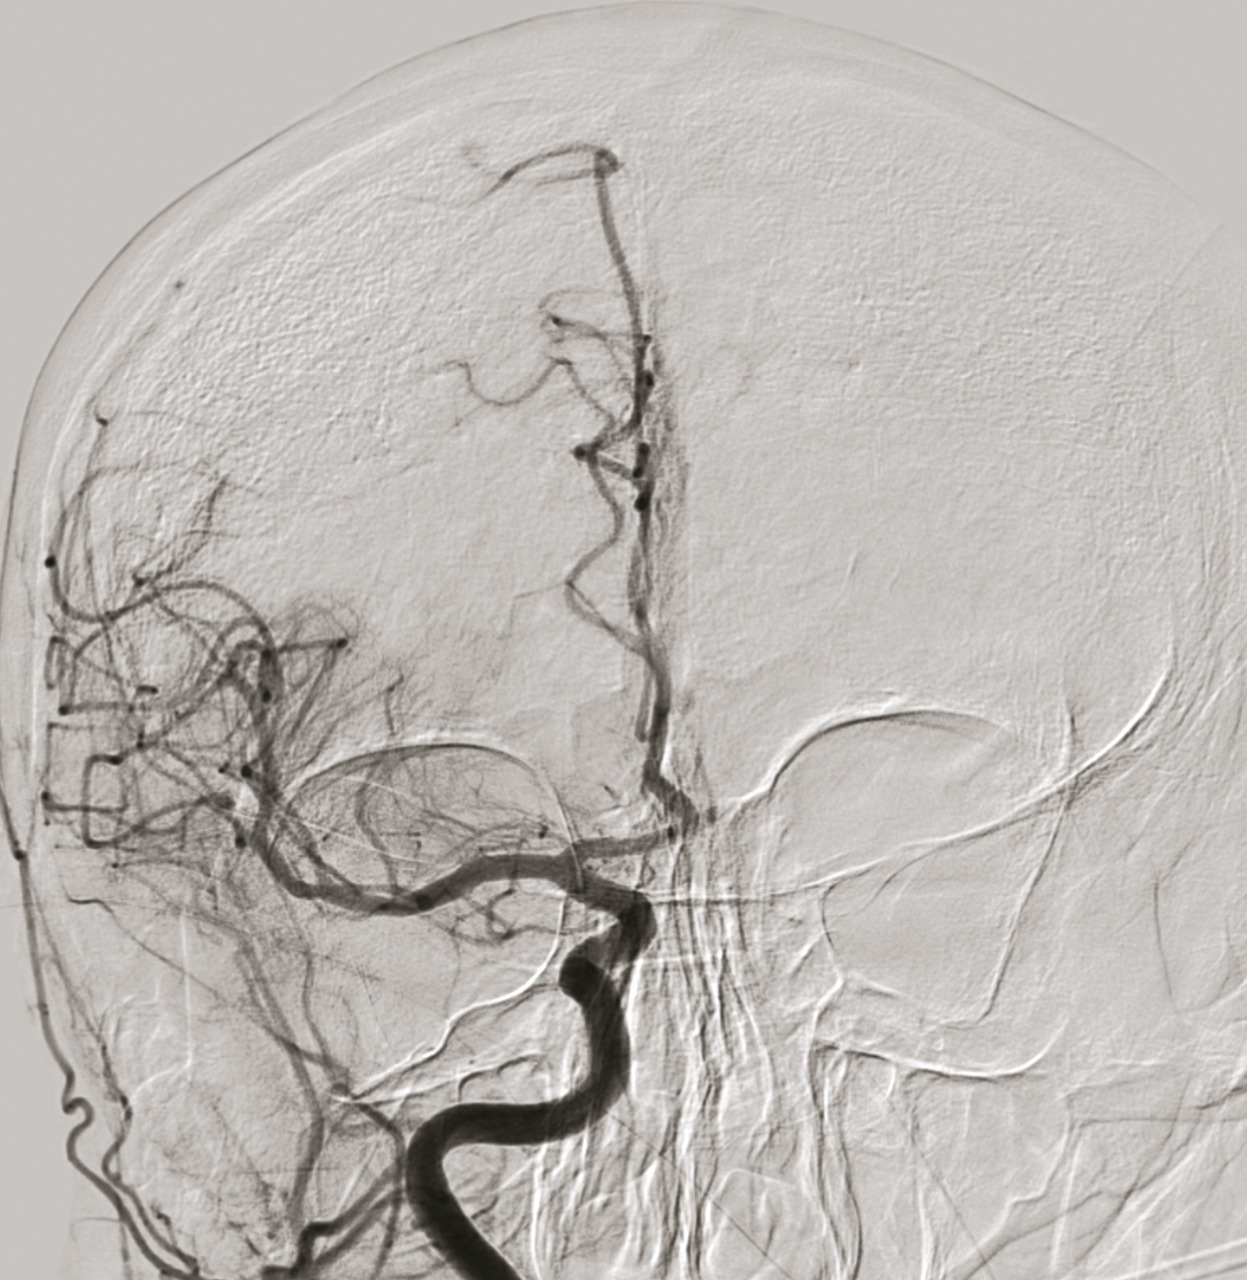

En 2015, cinq essais thérapeutiques ont prouvé l’efficacité de la thrombectomie mécanique en association à la thrombolyse IV dans le traitement des AVC ischémiques avec occlusion des artères de gros calibre de la circulation antérieure (artères carotide interne et moyenne proximale, fig. 1 à 4).6 La thrombectomie mécanique peut être réalisée avec des stents retriever (stents déployés mais non implantés) et/ou des dispositifs d’aspiration. L’effet de la thrombectomie mécanique est majeur, avec un nombre de patients à traiter de 2,6 pour éviter la dépendance,6 alors qu’il est estimé que pour 1 000 patients traités par thrombolyse IV, 41 éviteront la mort ou la dépendance.7 La thrombolyse IV est par ailleurs limitée par une augmentation du taux d’hémorragie intracrânienne symptomatique responsable d’une surmortalité durant les 7 premiers jours ; de faibles taux de recanalisation (au mieux 30 %, alors que la thrombectomie mécanique permet des taux de 80 à 90 %) en cas d’occlusion proximale intracrânienne ; sans oublier de nombreuses contre-indications (traitements anticoagulants, chirurgie récente…).